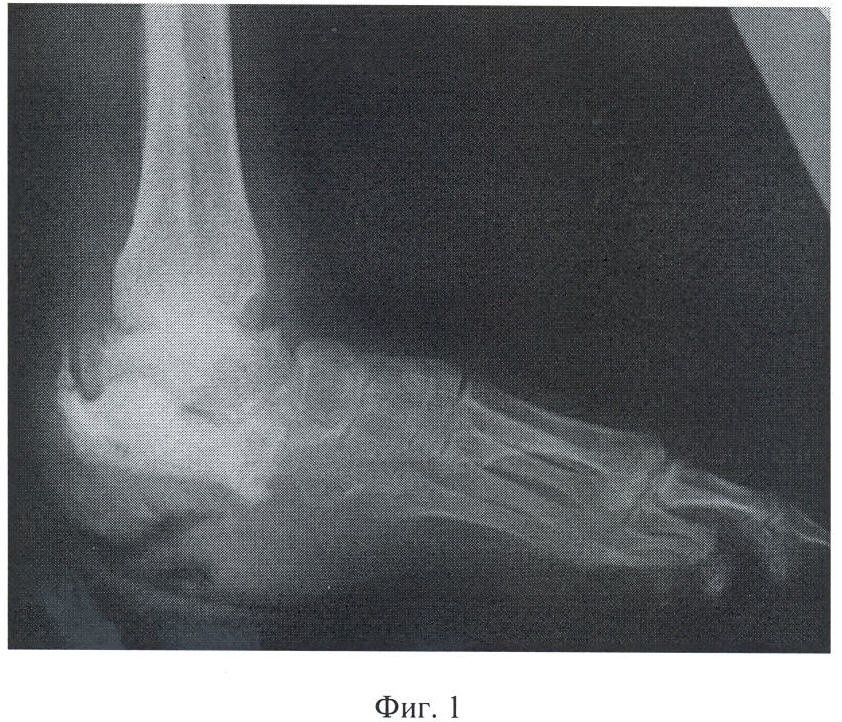

Фиг.1 – рентгенограмма левой стопы больного К. до лечения;

Фиг.2 – рентгенограмма левой стопы больного К. после выполнения остеосинтеза и секвестрнекрэктомии с удалением пяточной кости;

Больной К., 26 лет, поступил в клинику РНЦ «ВТО» имени акад. Г.А.Илизарова с диагнозом: хронический посттравматический остеомиелит левой пяточной кости, свищевая форма. Несращение дужек L4-L5. Нижний равномерный спастический парапарез до моноплегии в стопе слева.

Для ликвидации остеомиелитического процесса больному первоначально выполнена радикальная секвестрнекрэктомия с удалением пяточной кости, удаление хрящей в голеностопном и таранно-ладьевидном суставах; остеосинтез аппаратом внешней фиксации.

В ходе операции после анестезии и обработки операционного поля три спицы провели на уровне проксимальной, две – средней и три – дистальной трети берцовых костей. Таранную кость фиксировали двумя спицами, кости предплюсны и плюсневые кости – тремя спицами. В натянутом состоянии спицы закрепили на установленных в их проекции опорах, которые соединили между собой резьбовыми стержнями и шарнирными узлами.

Через разрез мягких тканей по наружной поверхности стопы осуществили доступ к пораженному отделу стопы и произвели радикальную секвестрнекрэктомию с удалением пяточной кости. Одновременно сняли хрящ с суставных поверхностей голеностопного и таранно-ладьевидного сочленений. После выполнения контрольной рентгенографии рану ушили с установкой дренажной системы.